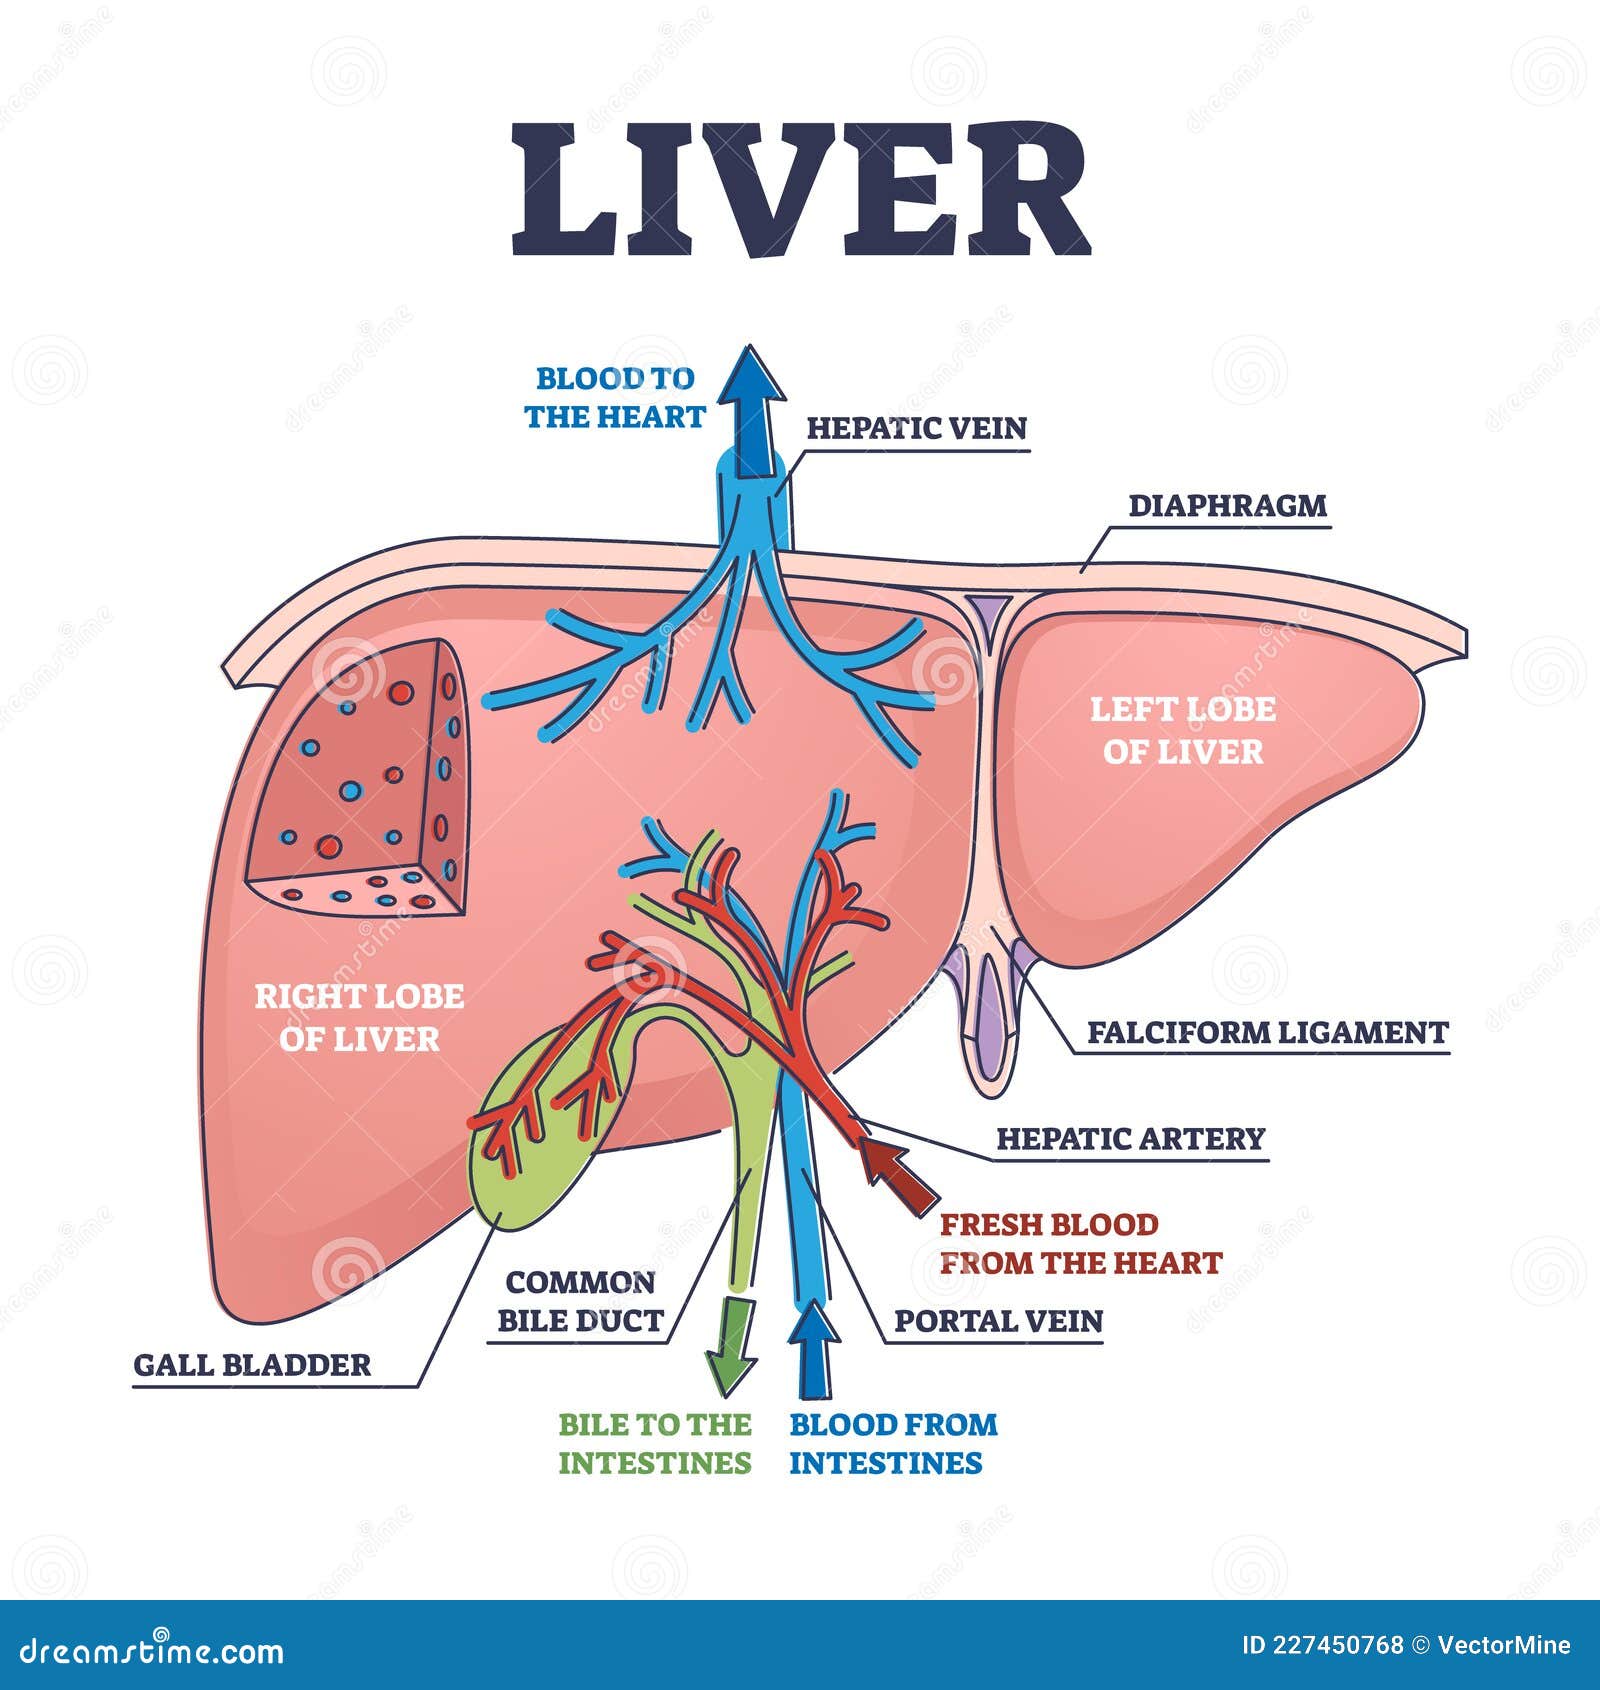

Картинки с надписью Liver: Как выбрать и использовать